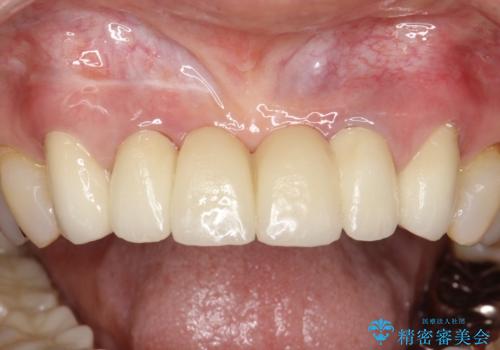

→根管治療終了後、ファイバーコアを築造し、新しいセラミックブリッジを製作した。

かぶせ物の種類:PFZ standard